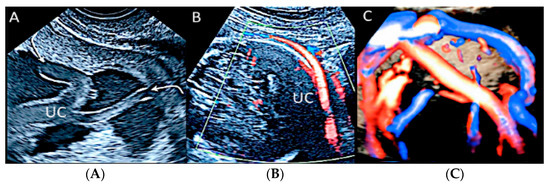

3.2. Umbilical Cord Anomalies

3.2.1. Nuchal Cords

3.2.2. Vasa Praevia

3.2.3. Velamentous Umbilical Cord Insertion

3.2.9. Umbilical Cord Cyst

3.2.10. Single Umbilical Artery

3.2.11. Umbilical Cord Varix